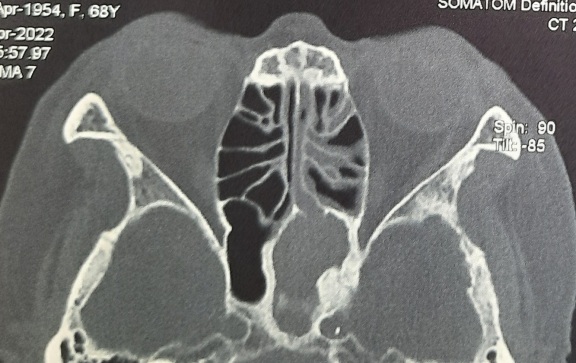

Hình ảnh CTscan